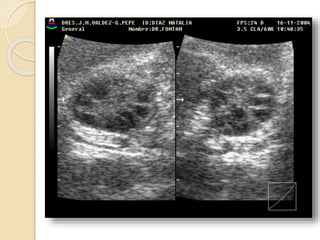

Poliquistosis Ovárica:

Se describe este síndrome como cambios

escleroquísticos en el ovario, mas

amenorrea, infertilidad e hirsutismo.

Ecográficamente vamos a ver

agrandamiento de ambos ovarios con

quistes subcorticales de menos de 1cm.,

mas incremento de las dimensiones del

estroma y fibrosis subcapsular.